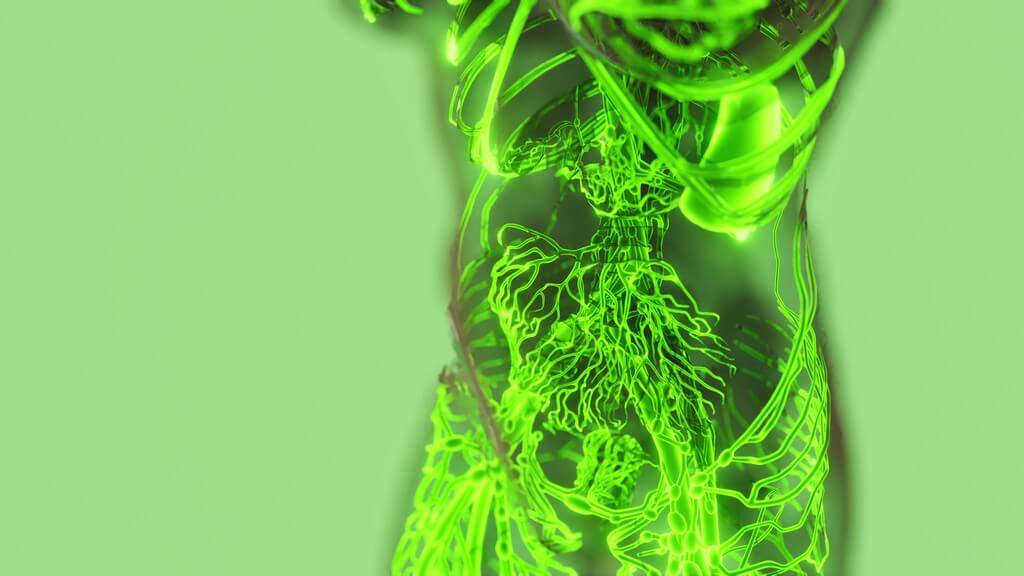

¿Qué es el sistema endocanabinoide?

Bueno, ¿han oído hablar alguna vez del sistema endocanabinoide? Esa maravilla de nuestro cuerpo que, créanme, juega un papelazo en mantenernos en equilibrio.. Estoy hablando de una red tan chévere que regula desde el apetito hasta el estado de ánimo, y claro, ¡tiene mucho que ver con esa hierbita que nos pone a pensar en la inmortalidad del cangrejo!

¿Cómo funcionan los endocanabinoides?

Los endocanabinoides tienen un rol importante en nuestro cuerpo. Actúan como mensajeros, enviando señales a diferentes partes para que hagan su trabajo. Imagina que son como emails que tu cuerpo se manda a sí mismo para mantener todo en orden.

Estas sustancias se pegan a lugares especiales llamados receptores de cannabinoides que están por todo el cuerpo.

Dos tipos principales de estos receptores son los CB1 y los CB2. Los receptores CB1 están en el cerebro y afectan cosas como los pensamientos, sentimientos y movimientos. Por otro lado, los CB2 están más en partes del cuerpo que ayudan a defender contra enfermedades.

Cuando los endocanabinoides se unen a estos receptores, pueden ayudar a calmar el dolor o reducir la inflamación, que es cuando partes del cuerpo se ponen rojas o hinchadas.

¿Qué son los receptores de los cannabinoides?

Bien, ahora que sabemos cómo actúan los endocanabinoides, hablemos de los receptores de los cannabinoides. Son como cerraduras especiales en las células de nuestro cuerpo. Los endocanabinoides y las sustancias del cannabis, como el THC, son como llaves que abren estas cerraduras.

Cuando esto sucede, los receptores mandan señales a diferentes partes del cuerpo para decirles qué hacer.

Existen dos tipos principales que debes conocer: los receptores CB1 y CB2. Los CB1 están en el cerebro y los nervios. Controlan cosas como el ánimo y el dolor. Los CB2 están más en el sistema inmune y ayudan a manejar la inflamación.

Cada vez que usas cannabis, estas sustancias químicas interactúan con estos receptores de maneras que pueden ayudar a tu cuerpo de diferentes formas.

El sistema endocanabinoide y las células cerebrales

El sistema endocanabinoide juega un gran papel en nuestro cerebro. Tiene moléculas, como los endocanabinoides, que se parecen mucho a lo que tiene la marihuana. Estos se unen a sitios especiales en las células del cerebro llamados receptores.

Piensa en ello como llaves que abren puertas. Estas “puertas” controlan cómo nos sentimos, cómo pensamos y cómo actúa nuestro cuerpo.

Las células gliales son las ayudantes del cerebro y también trabajan con el sistema endocanabinoide. Cuando todo va bien, ayudan a mantener el cerebro sano y se aseguran de que todo funcione como debe.

Pero si algo no está bien, pueden proteger el cerebro y ayudar a arreglarlo. ¡Es impresionante cómo unas cosas tan pequeñas pueden hacer tanto!

Mejora de la inflamación por endocanabinoides

Los endocanabinoides pueden hacer que la inflamación en el cuerpo sea menos fuerte. Esto es bueno porque la inflamación puede causar dolor y daño a las partes del cuerpo. Los extractos de Cannabis sativa, que se toman por la boca, han mostrado que ayudan a prevenir esta inflamación.

Esto es importante para mantenernos saludables.

El CBD, que viene de las plantas de marihuana, juega un papel muy grande en este proceso. Esta sustancia ayuda a calmar la inflamación al ser inmunosupresor. Eso significa que reduce algunas sustancias químicas que nuestro cuerpo produce y que pueden causar inflamación.

Así que el CBD puede ser un gran amigo cuando se trata de cuidar nuestro sistema inmunológico.

THC y CBD en el sistema endocanabinoide

El THC y el CBD son como las llaves que abren puertas en nuestro cuerpo. Estas “puertas” son en verdad partes del sistema endocanabinoide. Este sistema tiene cosas llamadas receptores, y están por todo el cuerpo.

El THC se une a ellos y puede hacer que te sientas relajado o feliz. Pero espera, hay más: el CBD también se une a los receptores, pero de una manera que no te hace sentir raro. El CBD puede ayudar al cuerpo de diferentes formas, como mantener la calma o ayudar a que no te sientas adolorido.

Imagina que el THC y el CBD trabajan en equipo para mantener tu cuerpo funcionando bien.

Es genial cómo estas dos sustancias del cannabis pueden influir tanto en nosotros. El THC es el que tiene más fama porque es el que te coloca. Pero no hay que olvidar al CBD; aunque no te hace sentir ‘colocado’, tiene muchísimos beneficios para la salud.

Juntos, estos compuestos ayudan a nuestro sistema endocanabinoide a hacer un montón de cosas importantes, ¡como cuidar nuestras células cerebrales!

2-AG y el sistema endocanabinoide

El 2-AG es como un mensajero en nuestro cuerpo. Trabaja con el sistema endocanabinoide, que es superimportante para mantenernos saludables. Imagínate que tu cuerpo es una ciudad grande y el 2-AG son los correos que van de un lado a otro llevando información importante.

Él se une a los receptores CB1 y CB2, que están como policías en las calles de la ciudad, controlando el tráfico y cuidando que todo esté bien.

Este sistema con el 2-AG ayuda mucho a nuestras células cerebrales. Es como tener un superhéroe en nuestro cuerpo, siempre listo para cuidar que todo funcione de lo mejor. Además, el THC de la marihuana actúa parecido al 2-AG, pero viene de afuera, como una ayuda extra.

Esto puede ser bueno o malo, depende de cómo lo usemos. ¡Es como si tuviéramos poderes especiales dentro de nosotros!